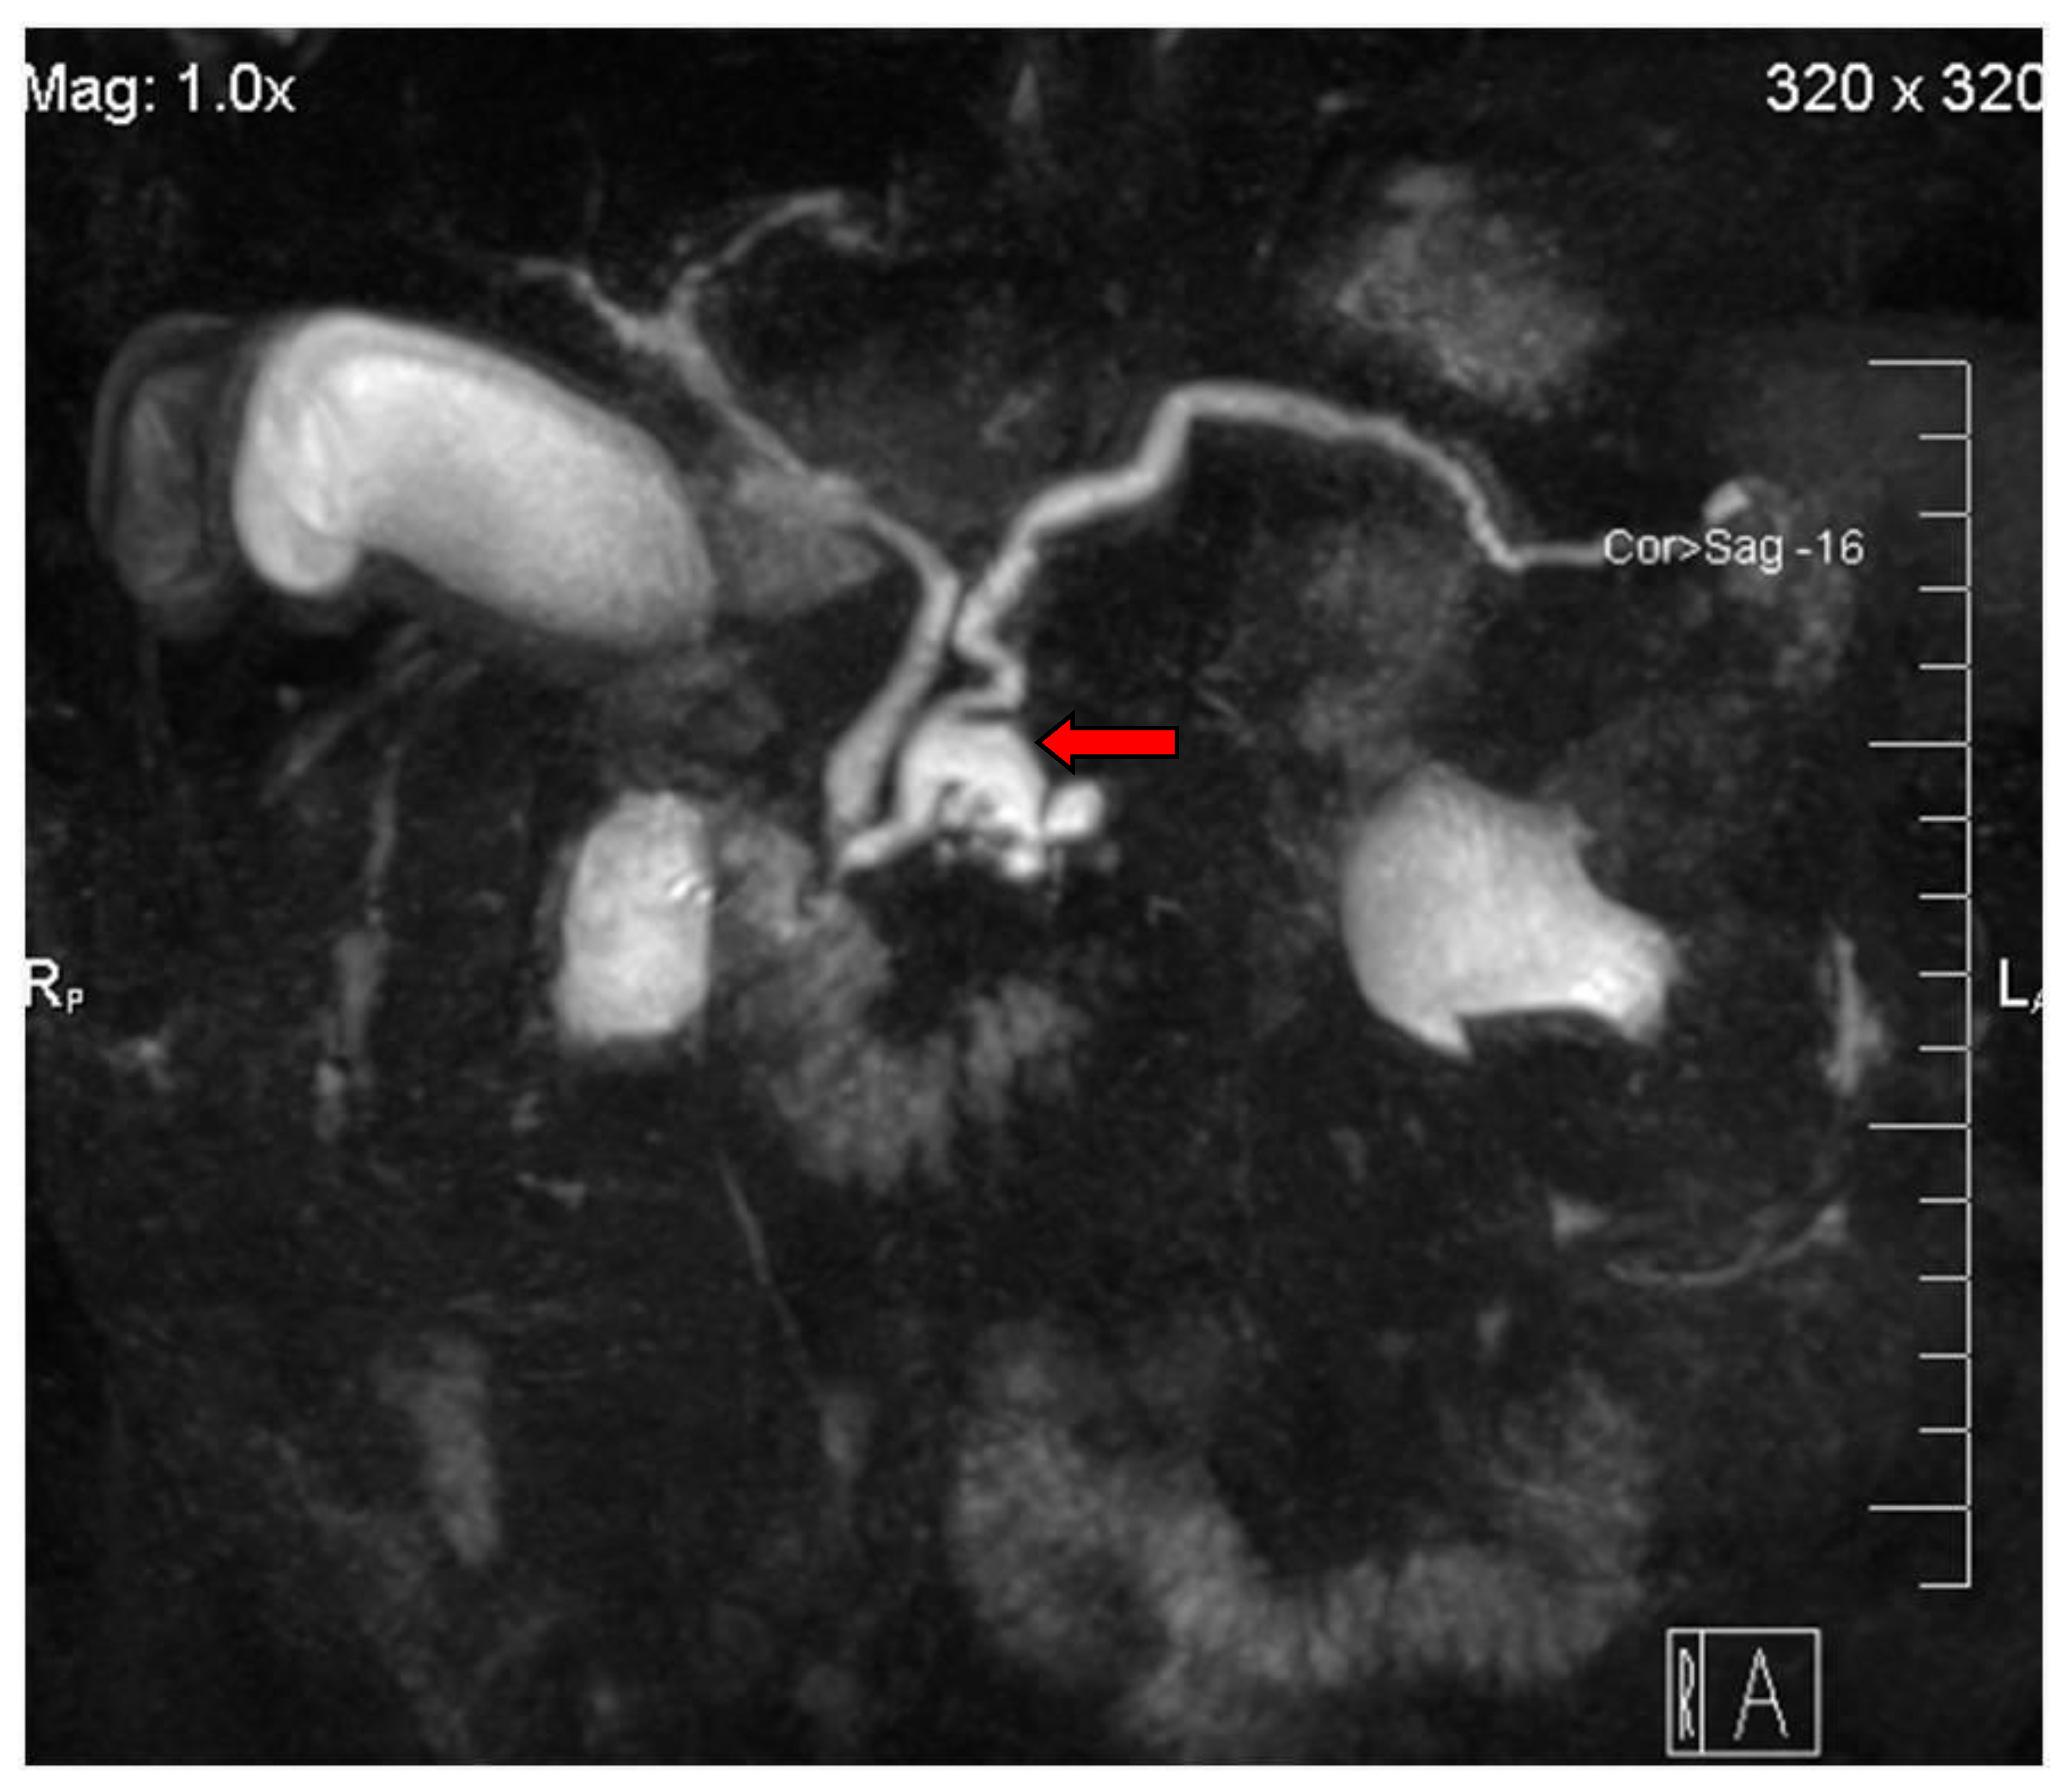

2. Imaging Findings